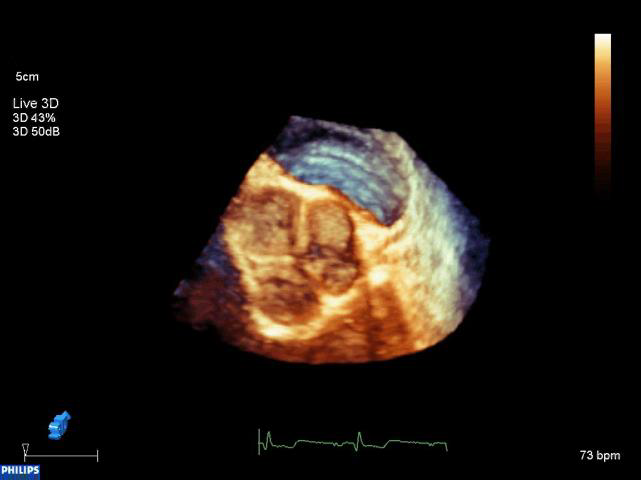

3D Ultrasound¶

While most of the clinical ultrasound are 2D image modality, modern US in fact has 3D capability. There are several mechanisms to achieve 3D US, with real-time 3D US achievd by ultrasound transducer equipped with a matrix-array of piezoelectric elements.

Figure 6:A 3D US volume depicting the Tricuspid valve at the right ventricle of the heart.

Compared to 2D US, 3D US in general has lower resolution and slower frame rate.